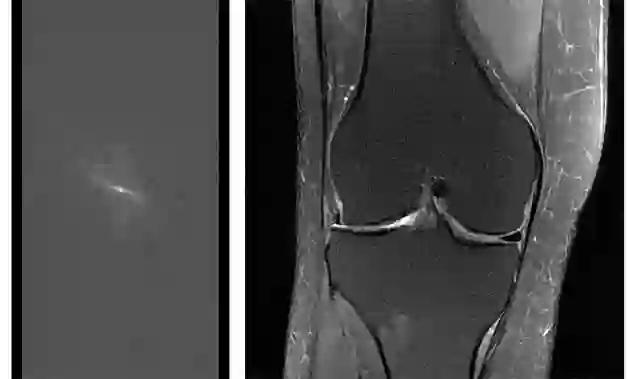

2018 年我们也开始了 fastMRI 项目(https://code.fb.com/ai-research/facebook-and-nyu-school-of-medicine-launch-research-collaboration-to-improve-mri/),这是我们与纽约大学医学院 (NYU School of Medicine) 开展的一项长期合作,旨在改善影像诊断技术,起初我们将 MRI 的扫描速度提高了 10 倍。目前的扫描需要一个小时或更长时间,对于一些患者或者在某些情况下,这肯定不行,该联合研究项目的目的是通过使用深度学习,从较少的原始扫描数据中生成图像,增加这种潜在的救生诊断工具的可用性。

fastMRI 的目的不是开发专有技术,而是加速领域内对这种技术的理解,纽约大学医学院已经做了迄今最大的充分采样的原始 MRI 数据集(数据集完全匿名)用于研究,也有开源模型来帮助更广泛的研究社区开始这项任务。我们还推出了一个在线排行榜(http://fastmri.org/leaderboards),大家可以发布自己的结果进行比较。

左图:转换成图像之前的原始 MRI 数据。为了获取诊断研究所需的全部原始数据,MRI 扫描会非常耗时。右图:从充分采样的原始数据中获得的膝关节重建 MRI 影像图。